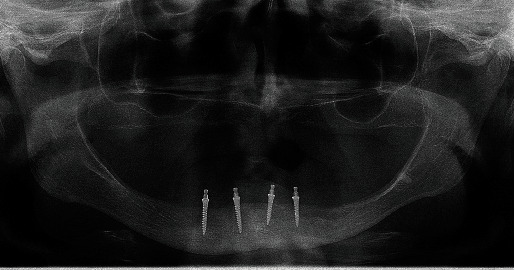

本临床报告描述了一名 78 岁的患者在无牙颌萎缩的下颌骨中植入微型种植体后,前庭活动粘膜直接接触微型种植体球头而引发眶下溃疡的情况,该患者已有 10 多年未佩戴传统下颌全口义齿。由于牙槽嵴严重萎缩,因此可以选择植入微型种植体(2.0 毫米宽),而无需进行广泛的外科手术。患者签署了知情同意书。种植体植入几天后,在与微型种植体相对的右侧前庭活动粘膜上发现了损伤、炎症和压痕。炎症的原因是口周肌肉张力增加,将活动粘膜推向微型种植体头,造成机械性创伤。在正畸期间,口周肌张力增加,将嘴唇和脸颊的粘膜推向残留的牙脊,使食物得以粉碎。由于患者没有旧的下颌义齿来覆盖微型种植体头,为了治疗持续性褥疮,在微型种植体头周围放置了大量牙科复合树脂,并进行了光固化处理,以保护粘膜免受进一步的机械性创伤。此外,还进行了前庭成形术(拔除活动附着物并加深前庭)。手术后,制作了一个类似于咬合缘的硅胶夹板,以保护粘膜,使加快脱落的药物就位,减少新假牙戴入前的口周肌肉张力,并防止活动组织复发。定制印模、颌骨关系确定和人工牙试戴都是在缝合线仍在原位的情况下进行的。安装假牙和植入种植体后,医生嘱咐患者戴着假牙睡觉,以保护活动粘膜。一年后,几乎没有观察到种植体周围边缘骨质流失,附着粘膜和种植体周围粘膜健康,患者非常满意。

This clinical report describes how a decubital ulcer arose from the direct contact of the vestibular movable mucous membrane against mini-implant balled-type heads after the mini-implant insertion in the edentulous atrophic mandible of a 78-year-old patient who was not wearing a conventional mandibular complete denture for more than 10 years. Due to severe alveolar ridge atrophy, mini-implant insertion (2.0 mm wide) was an option without extensive surgical procedures. The patient signed the informed consent. A few days after the implant insertion, injury, inflammation, and induration of the vestibular movable mucous membrane were observed on the movable vestibular mucosa on the right side, opposing the mini-implants. The cause of inflammation was attributed to increased perioral muscle tonus which pushed the movable mucosa onto the mini-implant heads and caused mechanical trauma. During the period of edentulism, the perioral muscle tonus increased, directing the mucous membrane of the lips and cheeks against residual ridge to enable food comminution. To treat the persistent decubitus, a bulk of dental composite resin was placed around mini-implant heads and light-cured to protect the mucosa from further mechanical trauma, as the patient did not possess an old mandibular denture to cover the mini-implant heads. Vestibuloplastic surgery (disinsertion of movable attachments and deepening of the vestibulum) was also done. After the surgery, a silicone splint, resembling an occlusal rim, was made to protect the mucous membrane, keep medicaments for faster epitalization in place, to decrease perioral muscle tonus before the new dentures' delivery, and to prevent movable tissue relapse. The custom impression, jaw relationship determination, and try-in of the artificial teeth setup were made with sutures still in place. After the denture delivery and implant loading, the patient was instructed to sleep with the dentures to protect the movable mucous membrane. One year later, almost no peri-implant marginal bone loss was observed, attached and peri-implant mucosa were healthy, and the patient was delighted.